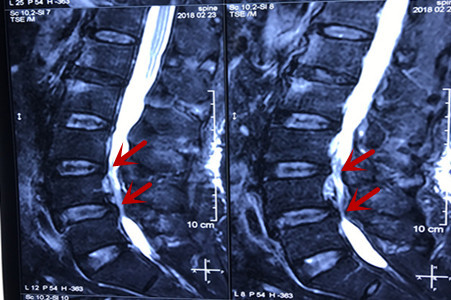

L4-5间盘突出伴椎管狭窄,L5-S1间盘突出。发病三个月前疼的难隐在能行走,后卧床养至今,左腿疼脚背麻能行走三十米就得停下休息。椎管狭窄手术费用 女人50岁前不该绝经